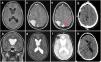

Presentamos el caso de un varón de 38 años remitido a nuestro servicio por la aparición brusca de diplopía con hemiparesia izquierda progresiva de 6 meses de evolución y caídas frecuentes. Tras realización de pruebas de imagen, se objetivan distintas lesiones intraaxiales y extraaxiales con diferente comportamiento radiológico decidiéndose un abordaje quirúrgico único para su exéresis. La anatomía patológica confirma cuatro variantes histológicas: meningioma (grado 1 y 2 [atípico]), subependimoma y cavernoma. Discutimos el papel teratogénico y efectos biológicos de las radiaciones ionizantes.

We present the case of a 38-year-old man referred to our department for a sudden diplopia with 6-month progressive left hemiparesis and frequent falls. After imaging tests, different intra and extraxial lesions with different radiological behavior were observed, performing a single surgical approach for their resection. The pathological anatomy confirms four histological variants: meningioma (grade 1 and 2 [atypical]), subependymoma, and cavernoma. We discuss the teratogenic role of ionizing radiation.